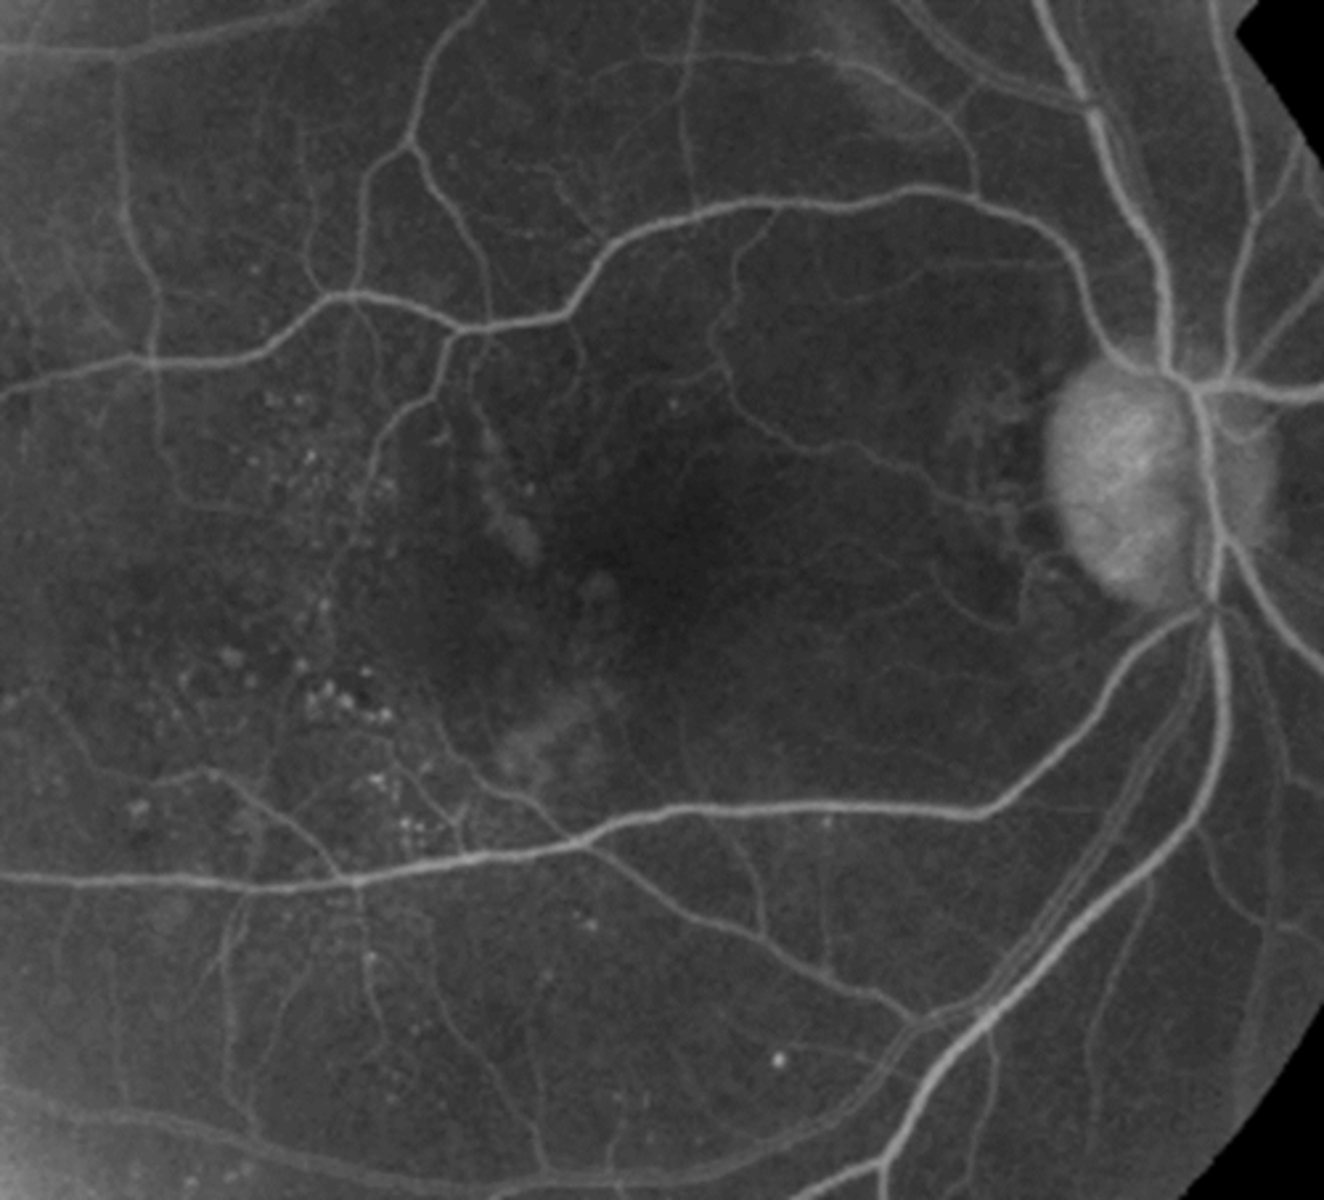

Microaneurysms- Grade 3 appearance

where are they usually located

how are they best visualized

Small out-pouch of an capillary wall

May be the direct result of an increase in pressure from a sclerosed arteriole

-Usually near AV crossing change

Often associated with CWS

Difficult to visualize

-Best seen with IVFA

Vascular Occlusion- Grade 3 appearance

-what is this a complication of

-what is it the most common cause of

Complications of retinal arteriosclerosis

-BRVO, CRVO (ischemic vs. non-ischemic): Most common etiology of BRVO

-Retinal, optic nerve, and/or anterior segment neovascularization

-BRAO, CRAO

-Retinal macroaneurysm